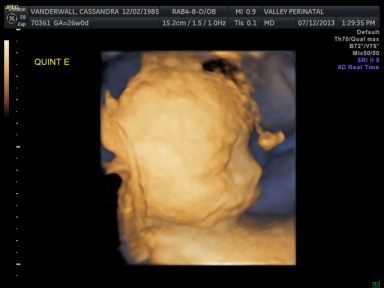

Friday we surpassed yet another milestone! The babies have been cooking for 7 months, which means we are now above the average gestational age for quintuplets. All of the babies were measured on Friday and they are all measuring within a day or two of the recommended size for babies at this point in pregnancy.

The biggest one in the bunch is Baby B at 2lbs and 12oz at the 62nd percentile. Little Elle Rose (Baby E) is the munchkin, but not by much as baby D and Theo (baby A) are also the same weight (2 ½ lbs) but just a bit longer. At this rate, when the baby’s are measured again at 32 weeks they will be about 1lb heavier each. Let’s just hope this Mama can keep up!